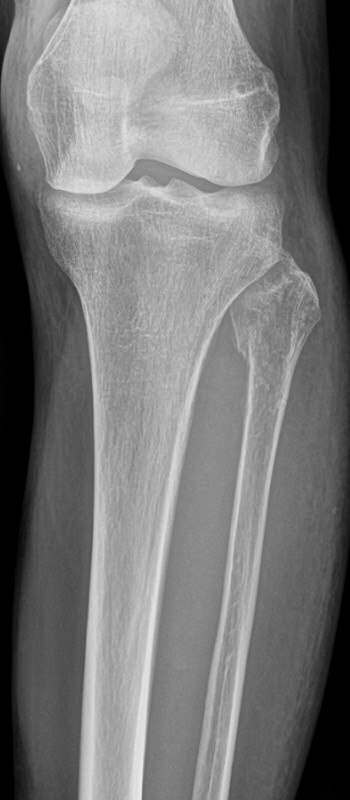

Maisonneuvefraktur

Proximal fibulafraktur (AO C3), ruptur av membrana interossea ned till fotleden och fraktur i mediala malleolen eller ruptur av lig. deltoideum.

Exempel på maisonneuvefraktur. Proximal spiralformad fibulafraktur, var svullen och ömmande runt båda malleolerna men ingen fraktur distalt.